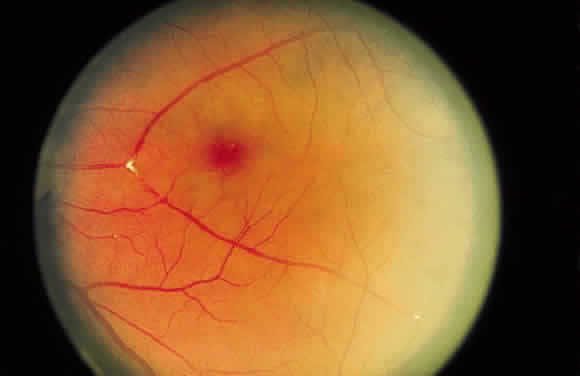

shape of the hemorrhage. Fresh hemorrhage on the retinal surface appears bright red, whereas fresh hemorrhage

beneath the retinal pigment epithelium seems much darker. A hemorrhage in the nerve fiber layer (Fig. 11A) dissects along the plane of the layer parallel to the orientation of

no such delineating structure is present. Therefore, a fresh

nerve fiber layer hemorrhage appears bright red and has feathery

borders, whereas a subpigment epithelial hemorrhage appears brown-black

and has sharp borders (Fig. 13).  Fig. 11. A. Section of retina with hemorrhage in the nerve fiber layer (between the two large arrows). Notice that the limits of the hemorrhage are not clearly defined, since

scattered red blood cells can be seen to the right of the right-hand

large arrow. This histologic picture corresponds to a clinically observed

fame-shaped hemorrhage with an indistinct border. The detached

posterior hyaloid is marked by four small arrows. B. Fundus photograph of nerve fiber layer hemorrhage. They are oriented parallel

to the plane of the internal limiting membrane. Because of their

dispersal within the ganglion cell layer, the borders are “feathery” (flame

shaped). Fig. 11. A. Section of retina with hemorrhage in the nerve fiber layer (between the two large arrows). Notice that the limits of the hemorrhage are not clearly defined, since

scattered red blood cells can be seen to the right of the right-hand

large arrow. This histologic picture corresponds to a clinically observed

fame-shaped hemorrhage with an indistinct border. The detached

posterior hyaloid is marked by four small arrows. B. Fundus photograph of nerve fiber layer hemorrhage. They are oriented parallel

to the plane of the internal limiting membrane. Because of their

dispersal within the ganglion cell layer, the borders are “feathery” (flame

shaped).